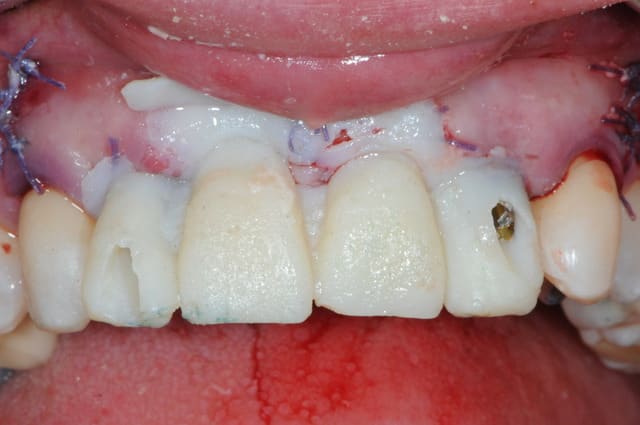

la prothèse immédiate grâce aux empreintes de départ.

ici la résine c'est du protemp 4, c'est super mais un peu gras.